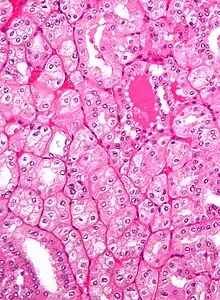

| Micrograph showing the most common type of kidney cancer (clear cell renal cell carcinoma). H&E stain. | |

The most common type of kidney malignancy is renal cell carcinoma,[31] which is thought to originate from cells in the proximal convoluted tubule of the nephron.[12][32] Another type of kidney cancer although less common, is transitional cell cancer (TCC) or urothelial carcinoma of the renal pelvis.[33] The renal pelvis is the part of the kidney that collects urine and drains it into a tube called the ureter.[33] The cells that line the renal pelvis are called transitional cells, and are also sometimes called urothelial cells. The transitional/urothelial cells in the renal pelvis are the same type of cells that line the ureter and bladder. For this reason TCC of the renal pelvis is distinct from RCC and is thought to behave more like bladder cancer.[33] Other rare types of kidney cancers that can arise from the urothelial cells of the renal pelvis are squamous cell carcinoma and adenocarcinoma.[12]

Renal cell carcinoma has been further divided into sub-types based on histological features and genetic abnormalities. The 2004 WHO Classification of the Renal Tumors of the Adults describes these categories:[37]

- Clear cell RCC